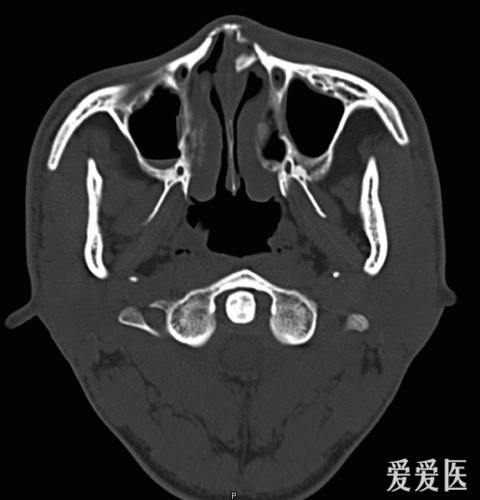

鼻骨骨折

鼻骨骨折影像学诊断